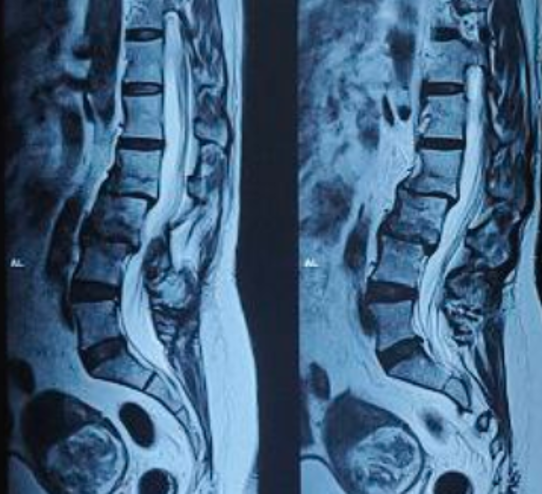

After Surgery Results

The surgeon removes the damaged disc or diseased bone, places a cage or bone graft between the vertebrae, and secures it with screws and rods. Over months, the bones heal together naturally. The surgical approach (front, back, or side) depends on the patient's specific condition and body type.

Patients usually stand or walk the next day. Office work can restart in 4-6 weeks, and full bone healing takes 3-6 months. In some cases, a brace may be used for extra support.